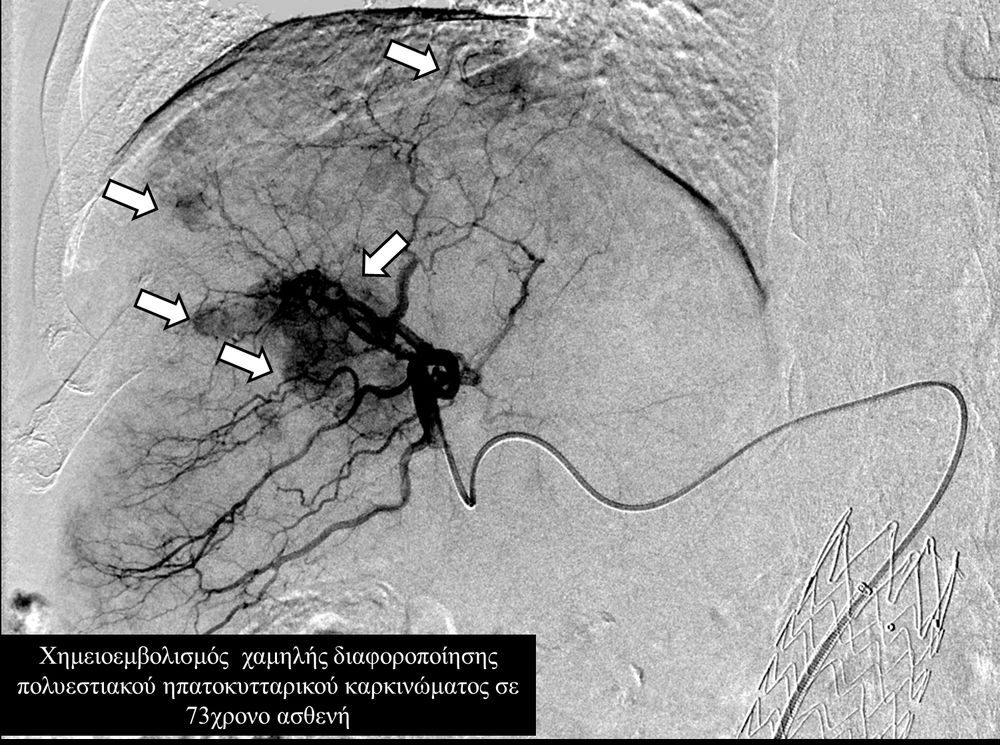

Ο χημειοεμβολισμός έχει καθιερωθεί σαν θεραπεία εκλογής στο ενδιάμεσο στάδιο του ηπατοκυτταρικού καρκινώματος.